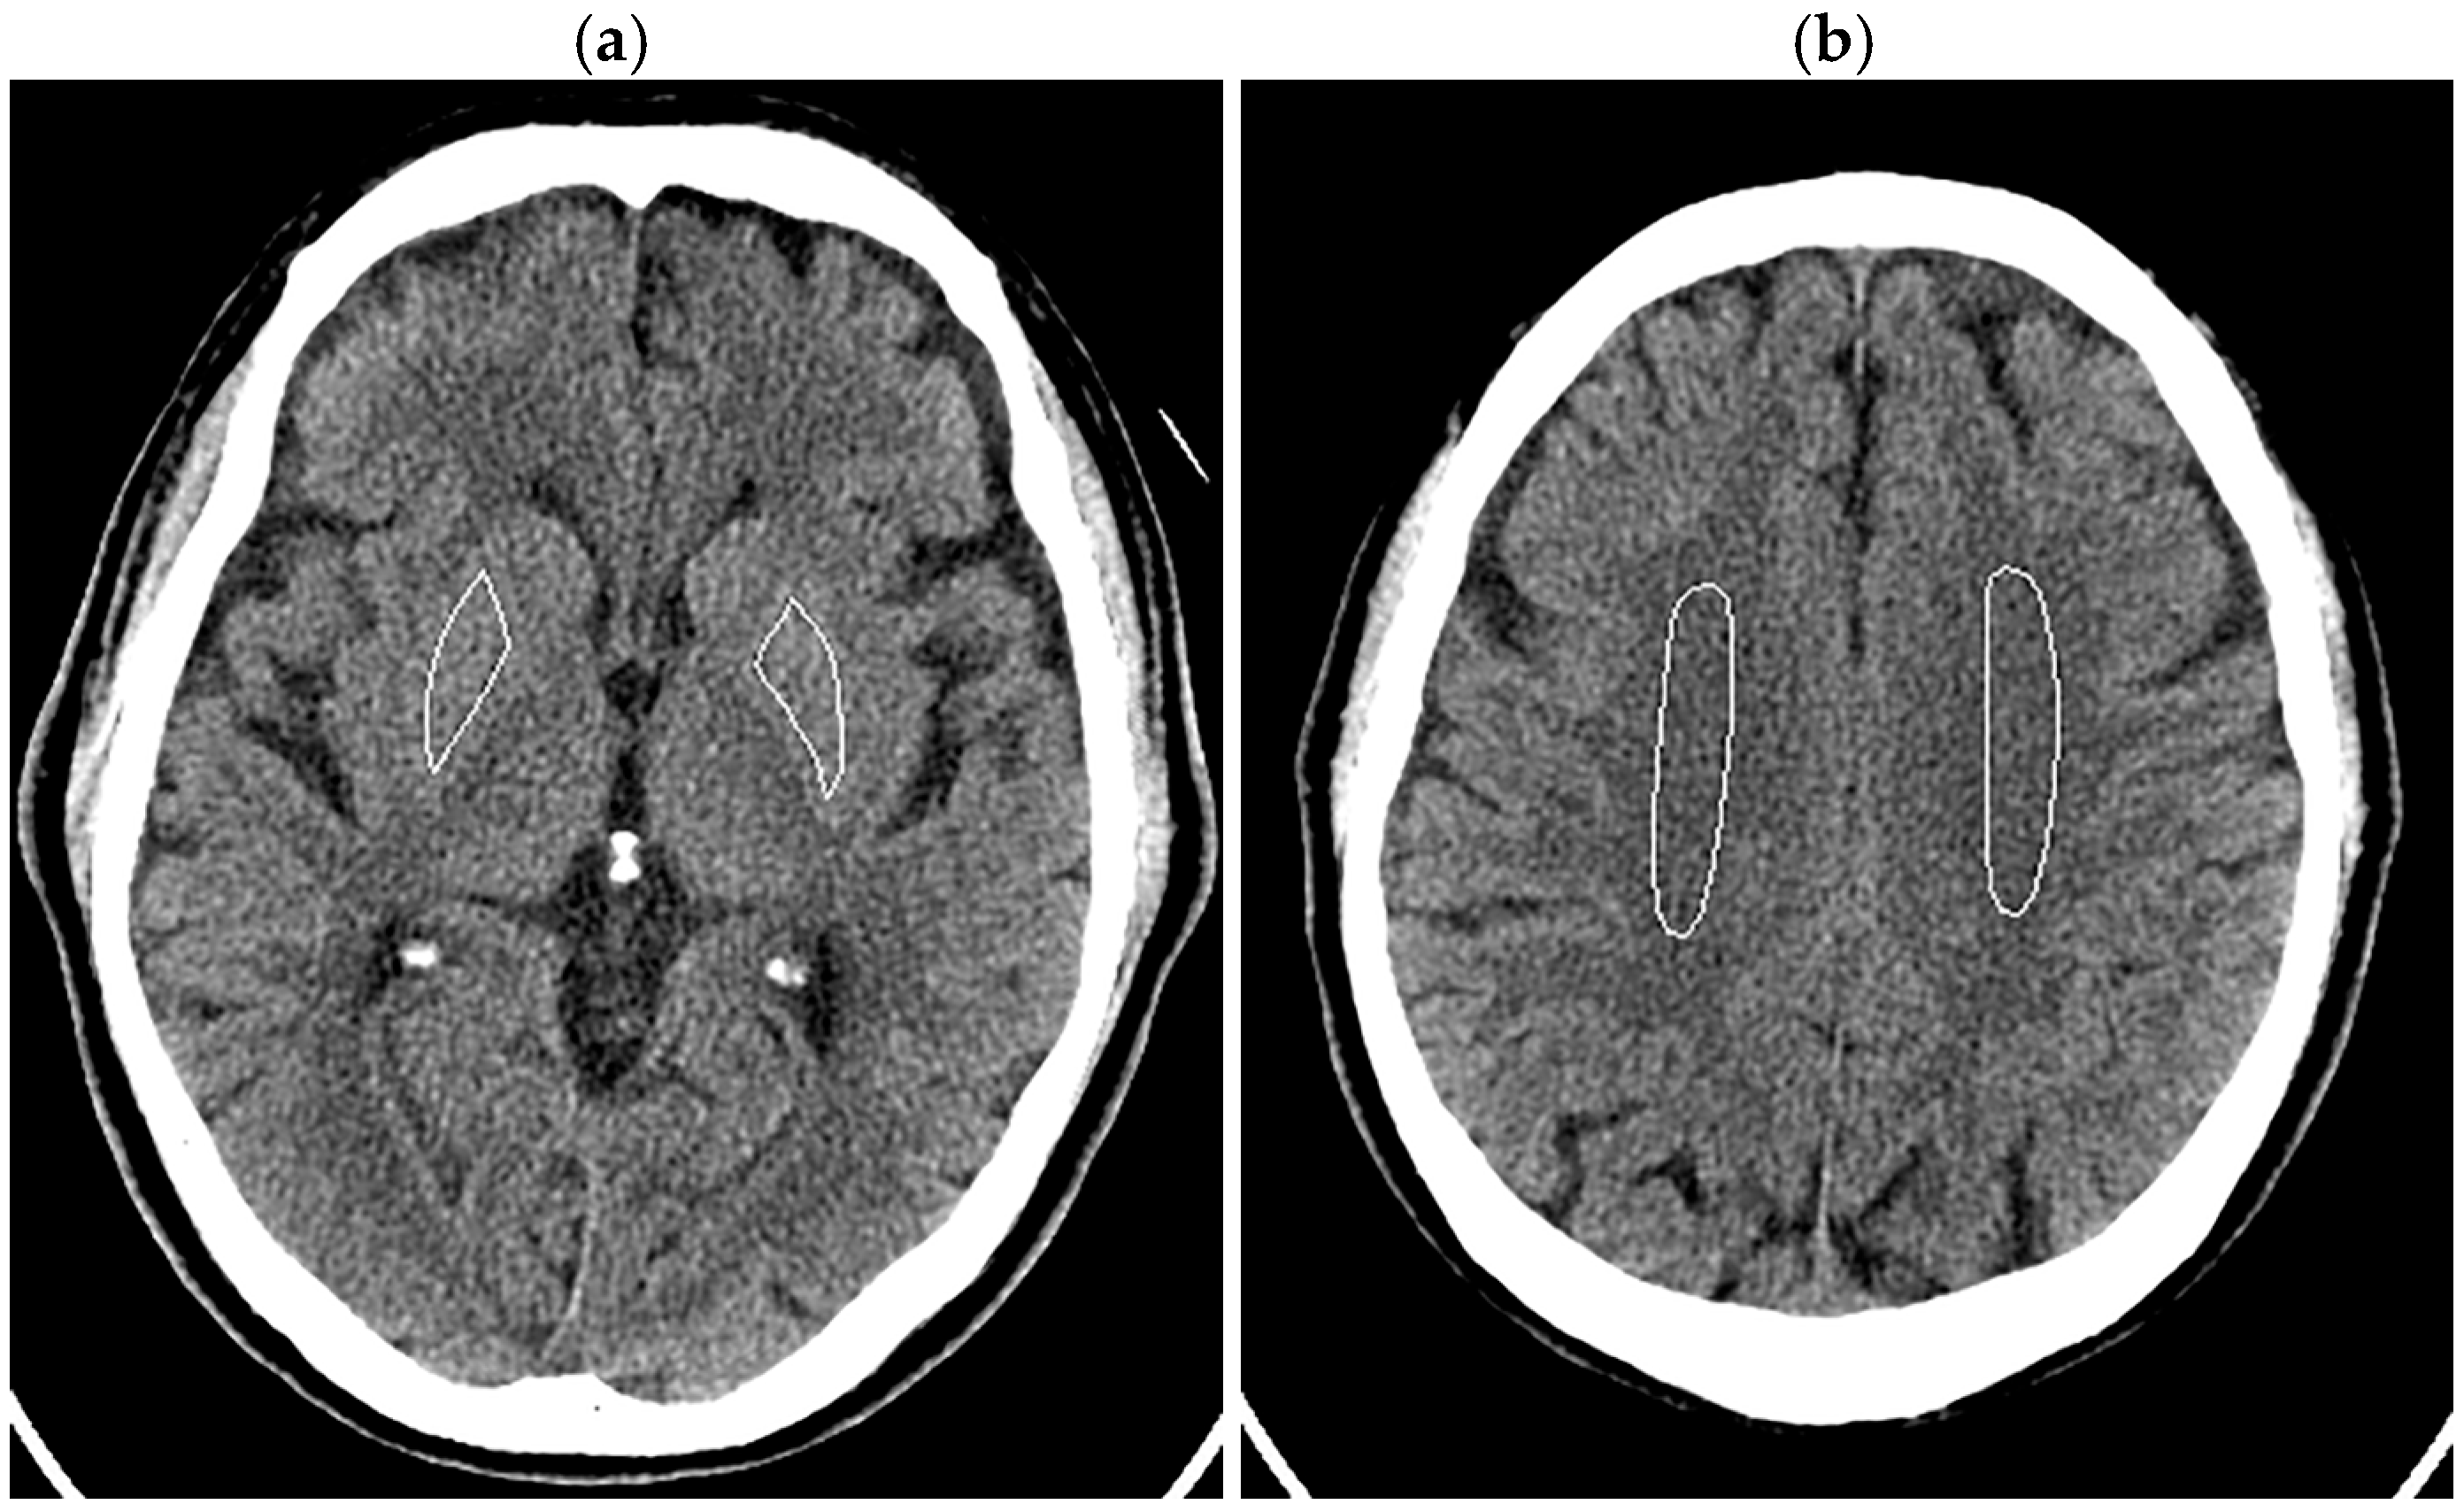

The patient’s head was imaged according to our routine clinical protocol. The tube current was modulated using inbuilt automatic exposure control software (Auto mA and Smart mA) with a noise index of 3.6, maximum mA of 350 mA, and minimum mA of 50 mA. Organ dose modulation was applied over the orbit to reduce radiation dose to the eye lens. This function selectively reduces radiation exposure from the anterior direction and does not change posterior exposure [31,32]. Image reconstruction was performed using FBP, three levels of DLR, and ten levels of HIR, similar to the phantom experiments. In image analysis, ROIs were manually drawn in bilateral lenticular nuclei (right 166.5 ± 26.6 mm2, left 158.5 ± 29.3 mm2), avoiding calcifications in the globus pallidus, and centrum semiovales (right 449.6 ± 136.0 mm2, left 432.6 ± 98.5 mm2) (Figure 2). The SD was obtained for each ROI, and the mean of the right and left values was defined as the image noises for the lenticular nucleus and centrum semiovale. Noise reduction ratios were calculated using the image noise for the FBP images as the reference.

Figure 2.

ROIs in the lenticular nuclei (a) and centrum semiovales (b) displayed on the 5 mm thick FBP images of the head of a 70-year-old male patient.